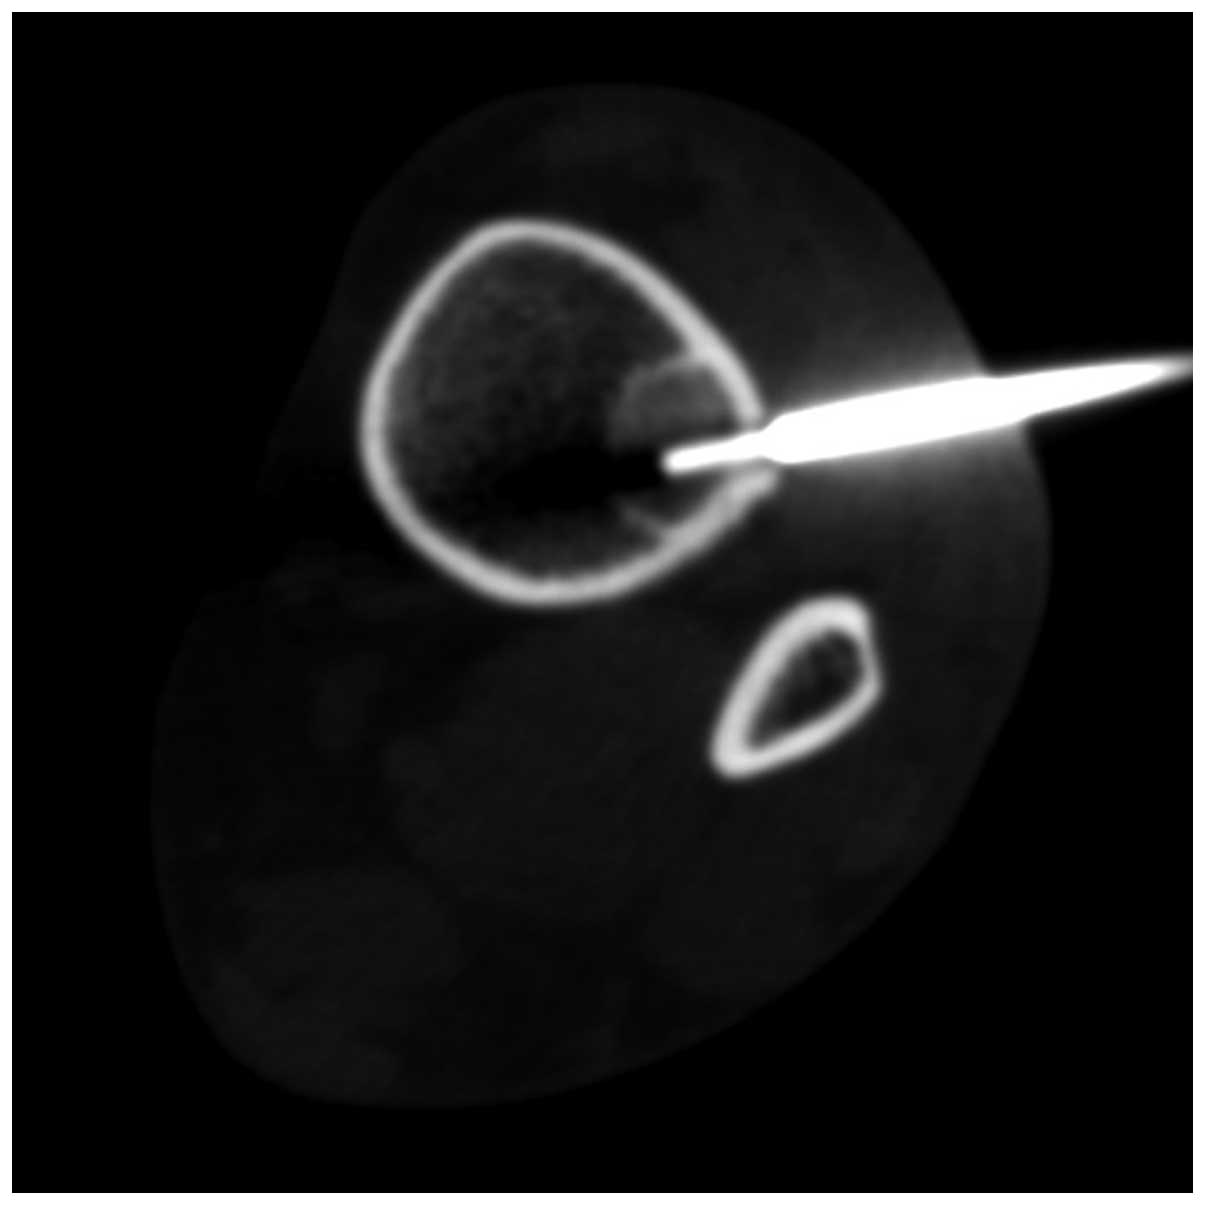

Desmoplastic fibroma of the distal tibia: A case report of a minimally invasive histological diagnosis

Desmoplastic fibroma (DF) is a benign, rare fibroblastic intraosseous neoplasm histologically resembling a desmoid soft tissue tumor. Although classified as benign, DF frequently exhibits an aggressive behavior, has a moderate‑to‑high recurrence rate, and often causes pathological fractures and extensive bone destruction. This case report presents an incidentally detected DF of the tibia, which was diagnosed using a minimally invasive approach. A 36‑year‑old African female patient was referred to the Department of Diagnostic Imaging of Arcispedale Santa Maria Nuova‑IRCCS (Reggio Emilia, Italy), to be examined by a computed tomography scan on an outpatient basis, after an x‑ray examination of the tibia, which was performed after an injury to exclude the presence of a fracture, revealed a hyperlucency of unknown origin. The aim of this study was to discuss the clinical, histological, immunohistochemical and radiographic characteristics of this rare neoplasm, with a focus on image‑guided bone biopsy.